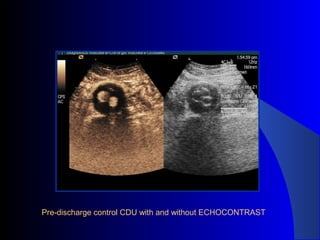

The document discusses the clinical application of the Endurant stent graft system in treating aorto-bisiliac aneurysms, detailing procedures performed on two male patients aged 72 and 73. Each patient had a history of dyslipidemia and carotid atherosclerosis, with procedures involving the bilateral bell bottom technique and the use of coils and fibrin glue. It includes pre-surgery imaging, intrasurgery angiography, and follow-up control scans to monitor outcomes.